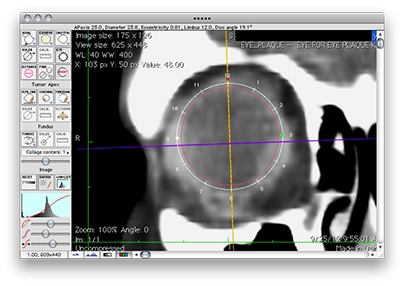

The other eye sizing tools

Open and load other CT or MR image planes in the same way as the axial image. The primary difference between image buffers in PS is that the eye sizing tools differ in appearance. Properly positioning and orienting the eye sizing tools on each image is the ONLY way PS can know how to display the image in 3D space and in 2D planar dosimetry space.

Axial

Equatorial

Sagittal

Tumor-Coronal

Tumor-Meridian